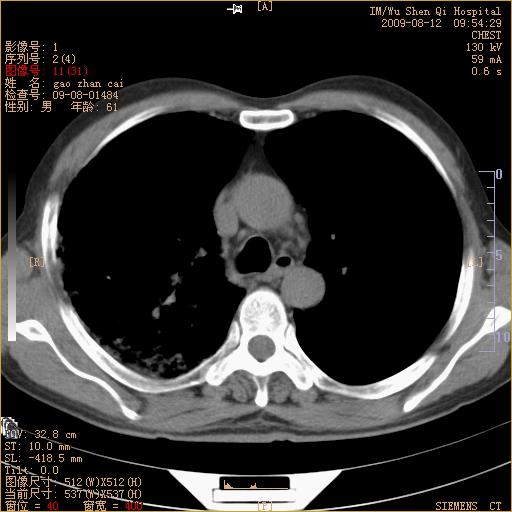

标题: CT21567:咳嗽,咳痰,发热半月余 [打印本页]

标题: CT21567:咳嗽,咳痰,发热半月余

考虑右肺支扩并感染可能,结核不除外,结核生化检查看看。

右肺门区占位待排(图片没有传完)

右肺上叶支扩并感染,肺间质纤维化,肺气肿,右肺门淋巴结肿大。建议抗炎治疗后复查。